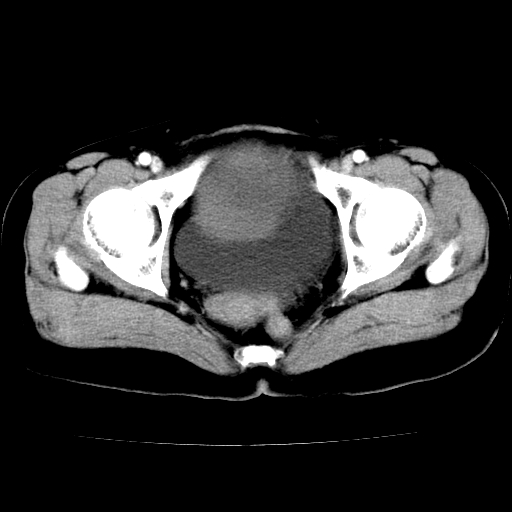

标题: CT24785:女,62岁,发现下腹部肿物半年。 [打印本页]

标题: CT24785:女,62岁,发现下腹部肿物半年。

女,62岁,发现下腹部肿物半年,下腹部不适。

卵巢囊腺瘤或囊腺癌,建议免疫组化实验

卵巢囊腺瘤或囊腺癌可能。

考虑附件粘液性囊腺瘤可能性大。

考虑附件囊腺癌。

考虑卵巢囊腺瘤或囊腺癌可能。